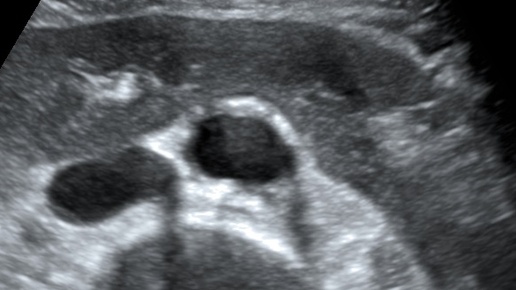

Подковообразная почка 01, типичные варианты (УЗИ)